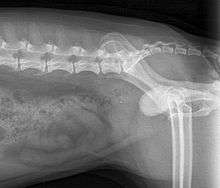

Diagnosis

When symptoms indicate bladder stones, the first step is usually to take an x-ray. Most types of stones will appear readily in an x-ray, urate and occasionally cystine stones being the most common exceptions. Stones smaller than three millimeters may not be visible.[3] Ultrasonography is also useful for identifying bladder stones. Crystals identified in a urinalysis may help identify the stones, but analysis of the stones is necessary for identification of the complete chemical composition.

Reasons for treatment of bladder stones include recurring symptoms and risk of urinary tract obstruction. Some stones can be dissolved using dietary modifications and/or medications. Small stones in female dogs may possibly be removed by urohydropropulsion, a nonsurgical procedure. Urohydropropulsion is performed under sedation by filling the bladder with saline through a catheter, holding the dog vertically, and squeezing the bladder to expel the stones through the urethra. Bladder stones can be removed surgically by a cystotomy, opening of the bladder. Stones lodged in the urethra can often be flushed into the bladder and removed, but sometimes a urethrotomy is necessary. In male dogs with recurrent urinary tract obstruction a scrotal urethrostomy creates a permanent opening in the urethra proximal to the area where most stones lodge, behind the os penis. In male cats, stones lodge where the urethra narrows in the penis. Recurrent cases can be treated surgically with a perineal urethrostomy, which removes the penis and creates a new opening for the urethra.